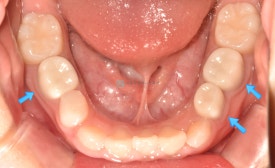

다음은 치아의 양 옆 사이가 썩어 가운데 낀 치아를 크라운한 케이스입니다.

치아의 양쪽에 사이충치가 있습니다.

양쪽 치아 레진치료 후, 가운데 치아 크라운치료 들어갑니다.삭제량이 크지 않아 신경치료 없이도 치료하였으며 잇몸 아래로 기구를 넣어 다듬는데도 잇몸에 출혈이 나지 않습니다.(잇몸이 크게 다치치 않습니다.)

맞는 사이즈의 크라운 접착 후 모습입니다. 역시 유치 지르코니아크라운은 예뻐요^^